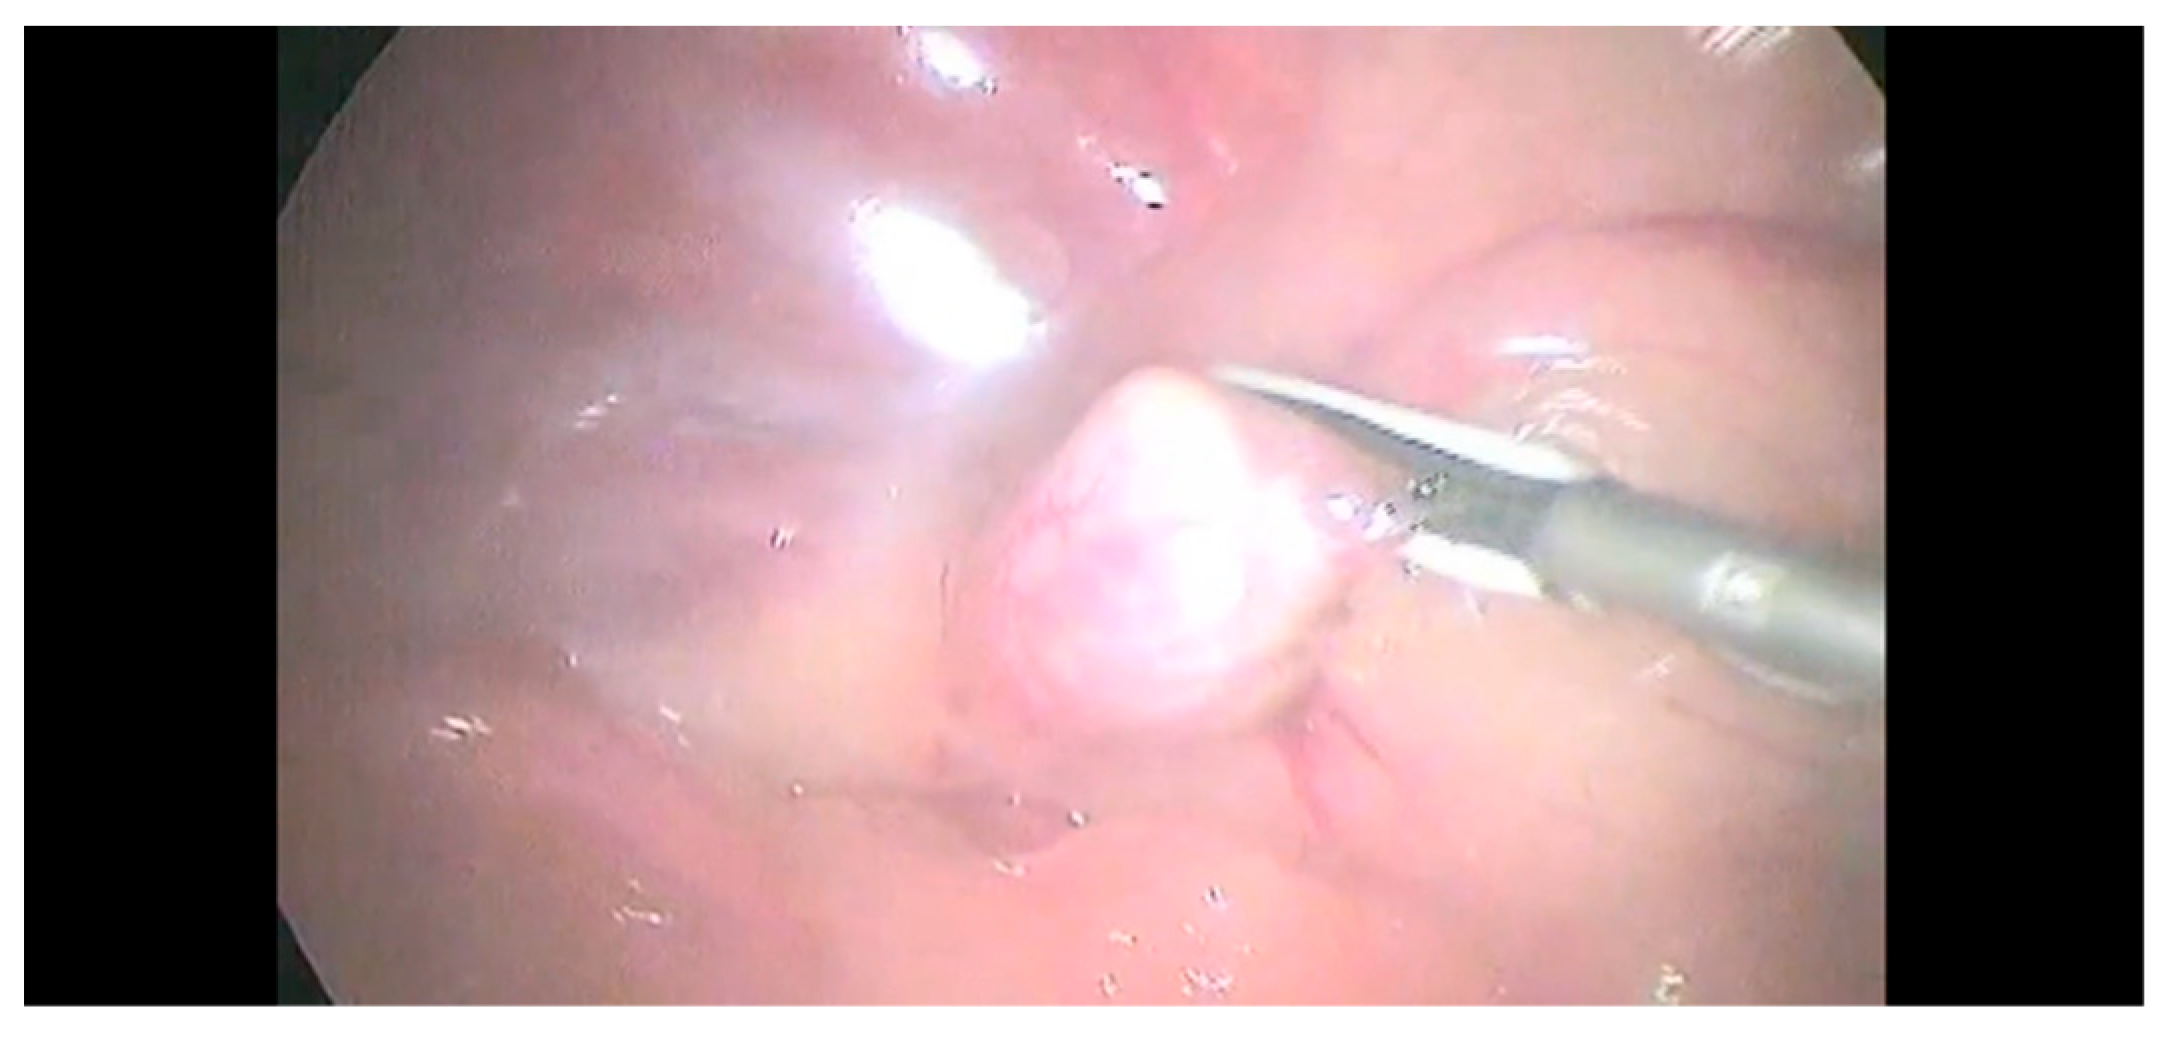

Anatomic differences between the right- and left-side adrenal glands required a different type of dissection. Babcock forceps, Kelly forceps, and the sealing device were introduced in T2 to obtain a better exposure of the right-side adrenal gland. The circumferential dissection of the adrenal gland was achieved using the 5 mm sealing device (Figure 3).

Figure 3.

The circumferential dissection of the adrenal gland was achieved using a 5 mm sealing device.